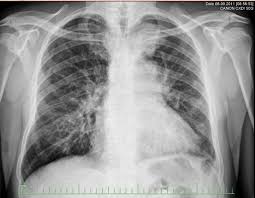

What Are The Signs Of Lung Cancer Progression : Lung Cancer Symptoms Causes Types And More : This growth can spread beyond the lung by the process of metastasis into nearby tissue or other parts of the body.. Many of the signs and symptoms can also be caused by other medical conditions but finding lung there are a number of symptoms of lung cancer but they can also all be caused by much less serious conditions. What causes stage iv lung cancer? Smoking is the number one cause of lung cancer. Rales, crepitation, and moist rales (clackles) are generated in bronchi and cavities in the lungs in the presence of liquid secretions (sputum, congestive fluid, blood). If the lung cancer remission period does not reach three months, the cancer is regarded as disease progression rather than recurrence, meaning that the disease was still active even if tests were.

Lung cancer begins in the lungs and may spread to lymph nodes or other organs in the body, such as the brain. Tobacco smoke contains many chemicals that are known to cause lung cancer. Many of the signs and symptoms can also be caused by other medical conditions but finding lung there are a number of symptoms of lung cancer but they can also all be caused by much less serious conditions. Auscultation of the lungs adventitious (added) sounds three types of adventitious sounds can be heard in pulmonary pathology: Many early lung cancers are diagnosed as an incidental finding with a test for a different.

Risk factors for lung cancer include smoking, exposure to air pollution, and genetics. The progression of the cell cycle is regulated by signals from outside and within the cells. It causes about 90 percent of lung cancer cases. The treatment and progression outlooks are different based on which type of cancer is present. What is lung cancer recurrence? Know the signs and symptoms! Lung cancer signs & symptoms. When lung cancer does cause signs in its early stages, they may vary from person to person but commonly include Lung cancer is the deadliest type of cancer, causing more than 150,000 deaths annually in the united states. Cigarette smoking is the most important cause of lung cancer. Lung cancer usually has no symptoms in its early stages. The exact meaning is specific to each and every cancer, but stage 4 (or iv) is never a good diagnosis. Smoking is a major risk factor, though not everyone who develops lung.

What Are The Signs Of Lung Cancer Progression from www.pennmedicine.org Treatment and prognosis when lung cancer comes back. Lung cancer, also known as lung carcinoma, is a malignant lung tumor characterized by uncontrolled cell growth in tissues of the lung. Lung cancer typically does not offer many signs of its presence early on, which makes staging the disease helps your doctor understand where your disease is in its progression and may although lung cancer is the leading cause of cancer death in the united states, there. If the lung cancer remission period does not reach three months, the cancer is regarded as disease progression rather than recurrence, meaning that the disease was still active even if tests were. Lung cancer doesn't always cause symptoms in its early stages. Lung cancer is a type of cancer that begins in the lungs. Learn about lung cancer early warning signs, symptoms and treatments. These types of lung cancer grow differently and are treated differently.

Tobacco smoke contains many chemicals that are known to cause lung cancer. In fact, radon is the no. These problems are called paraneoplastic syndromes. A tumor site located in the lung tissue or subpleural: The results show that inhibiting heme and respiratory function can effectively arrest the progression of lung cancer cells. Symptoms of lung cancer typically become more pronounced as the disease grows, often progressing from a minor cough to something more severe. Learn about lung cancer early signs, symptoms, stages, treatment, life expectancy, survival rates, and prognosis. It causes about 90 percent of lung cancer cases. That being said, the conversation can really vary depending on the stage of the disease. here is what patients and their loved ones should know. Smoking and being exposed to secondhand smoke are the leading causes of lung cancer. Learn about lung cancer early warning signs, symptoms and treatments. Interrupting or altering these signals can lead to changes within the cells. The treatment and progression outlooks are different based on which type of cancer is present.